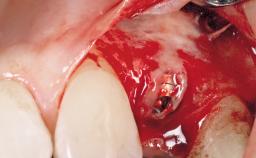

This 43-year-old male patient, a non-smoker, came to our practice because of a fracture of tooth 12 caused by a bicycle accident. Due to the combined para- and infrabony crown and root fracture, tooth extraction, and subsequent implant placement were suggested to the patient as the therapy of choice. The patient had high esthetic expectations with regard to the treatment outcome and asked for an immediate fixed provisional restoration. His individual esthetic risk profile summed up to a medium esthetic risk.

Placement Protocol Immediate implant placement

Socket Integrity Sufficient, with intact bone walls

Bone Volume Sufficient, with intact walls